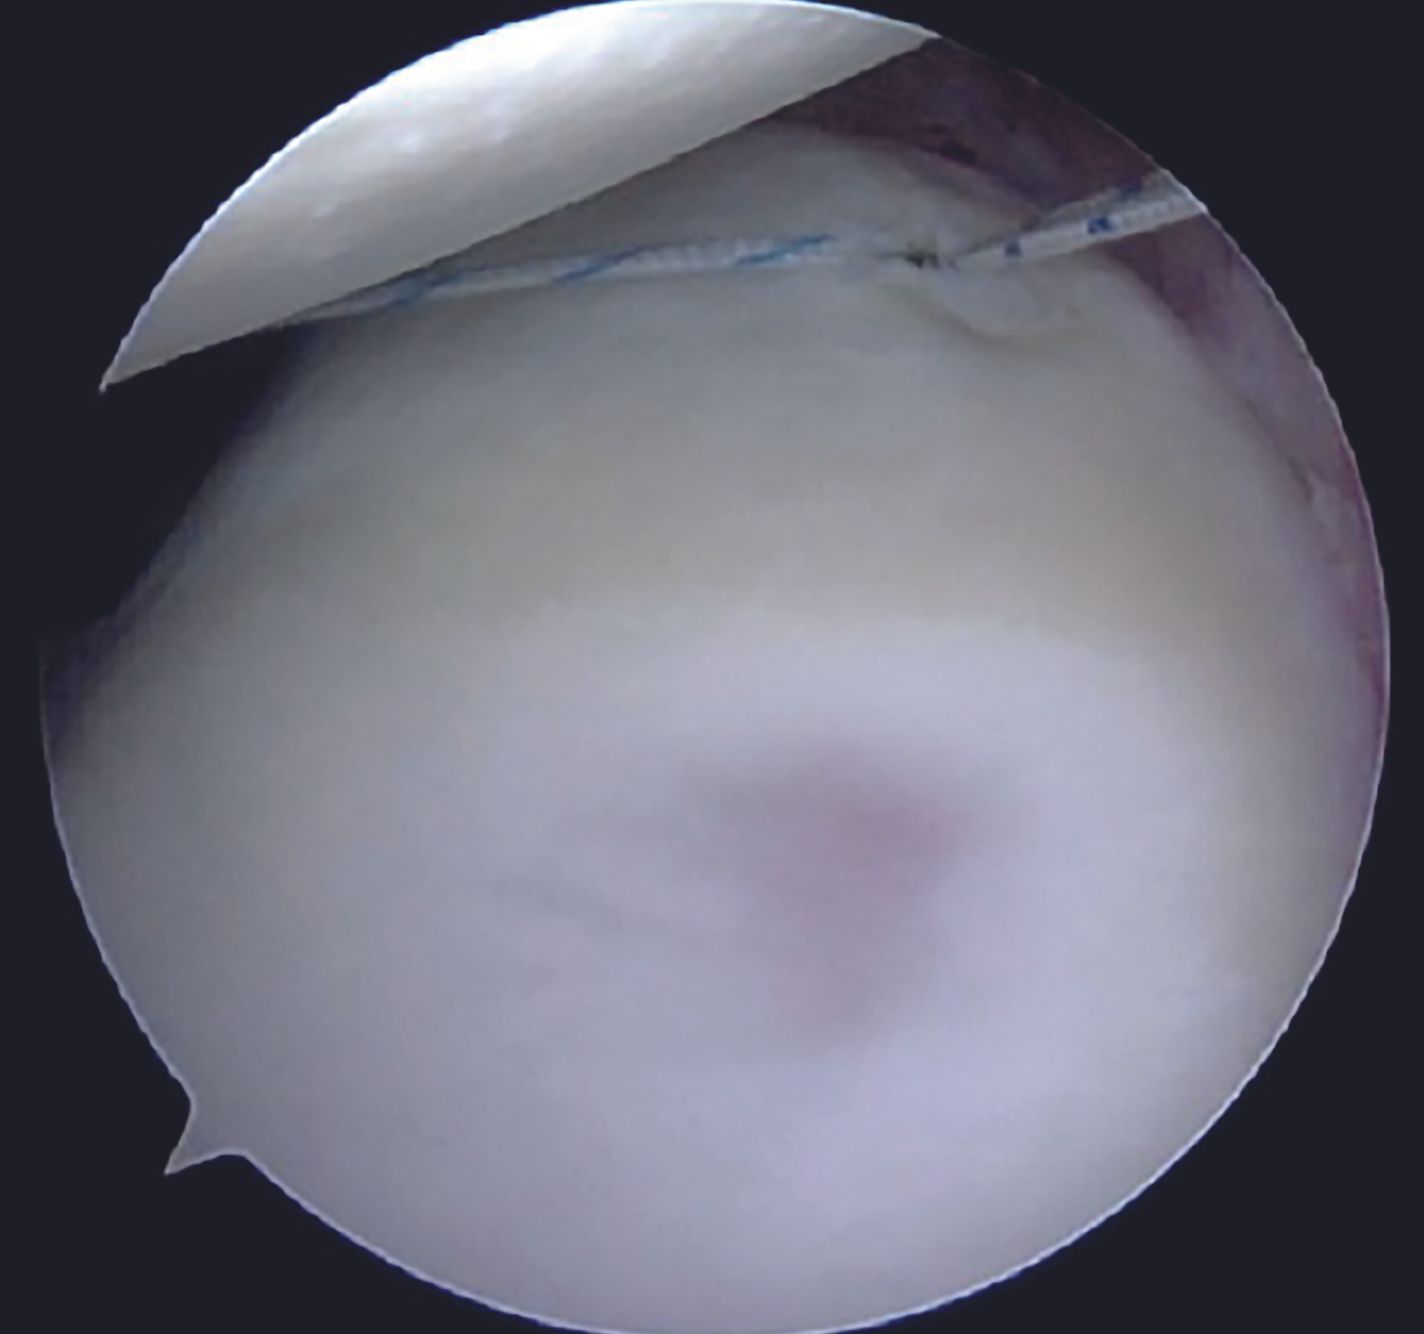

Anchor placement

For an isolated Bankart lesion, 3 anchors are usually sufficient. Our preferred choice for the anchor is 1.8mm all-suture anchor as the affected patients are young and thus possess a good quality of the subchondral bone. Advantages of all-suture anchors such as absence of metal implants, no interference with post-operative imaging, easier revision, are well known. Anchor with a tape is preferable to avoid cut-through through the labral tissue. Inferior most anchor is placed first at 5-5.30 O'clock position after drilling a hole using a sleeve through the AI portal (Figure 9). After tapping the anchor in, it is important to pull the tapes so that the anchor bunches up beneath the subchondral bone (Figure 10). Free passage of the tapes is ensured.